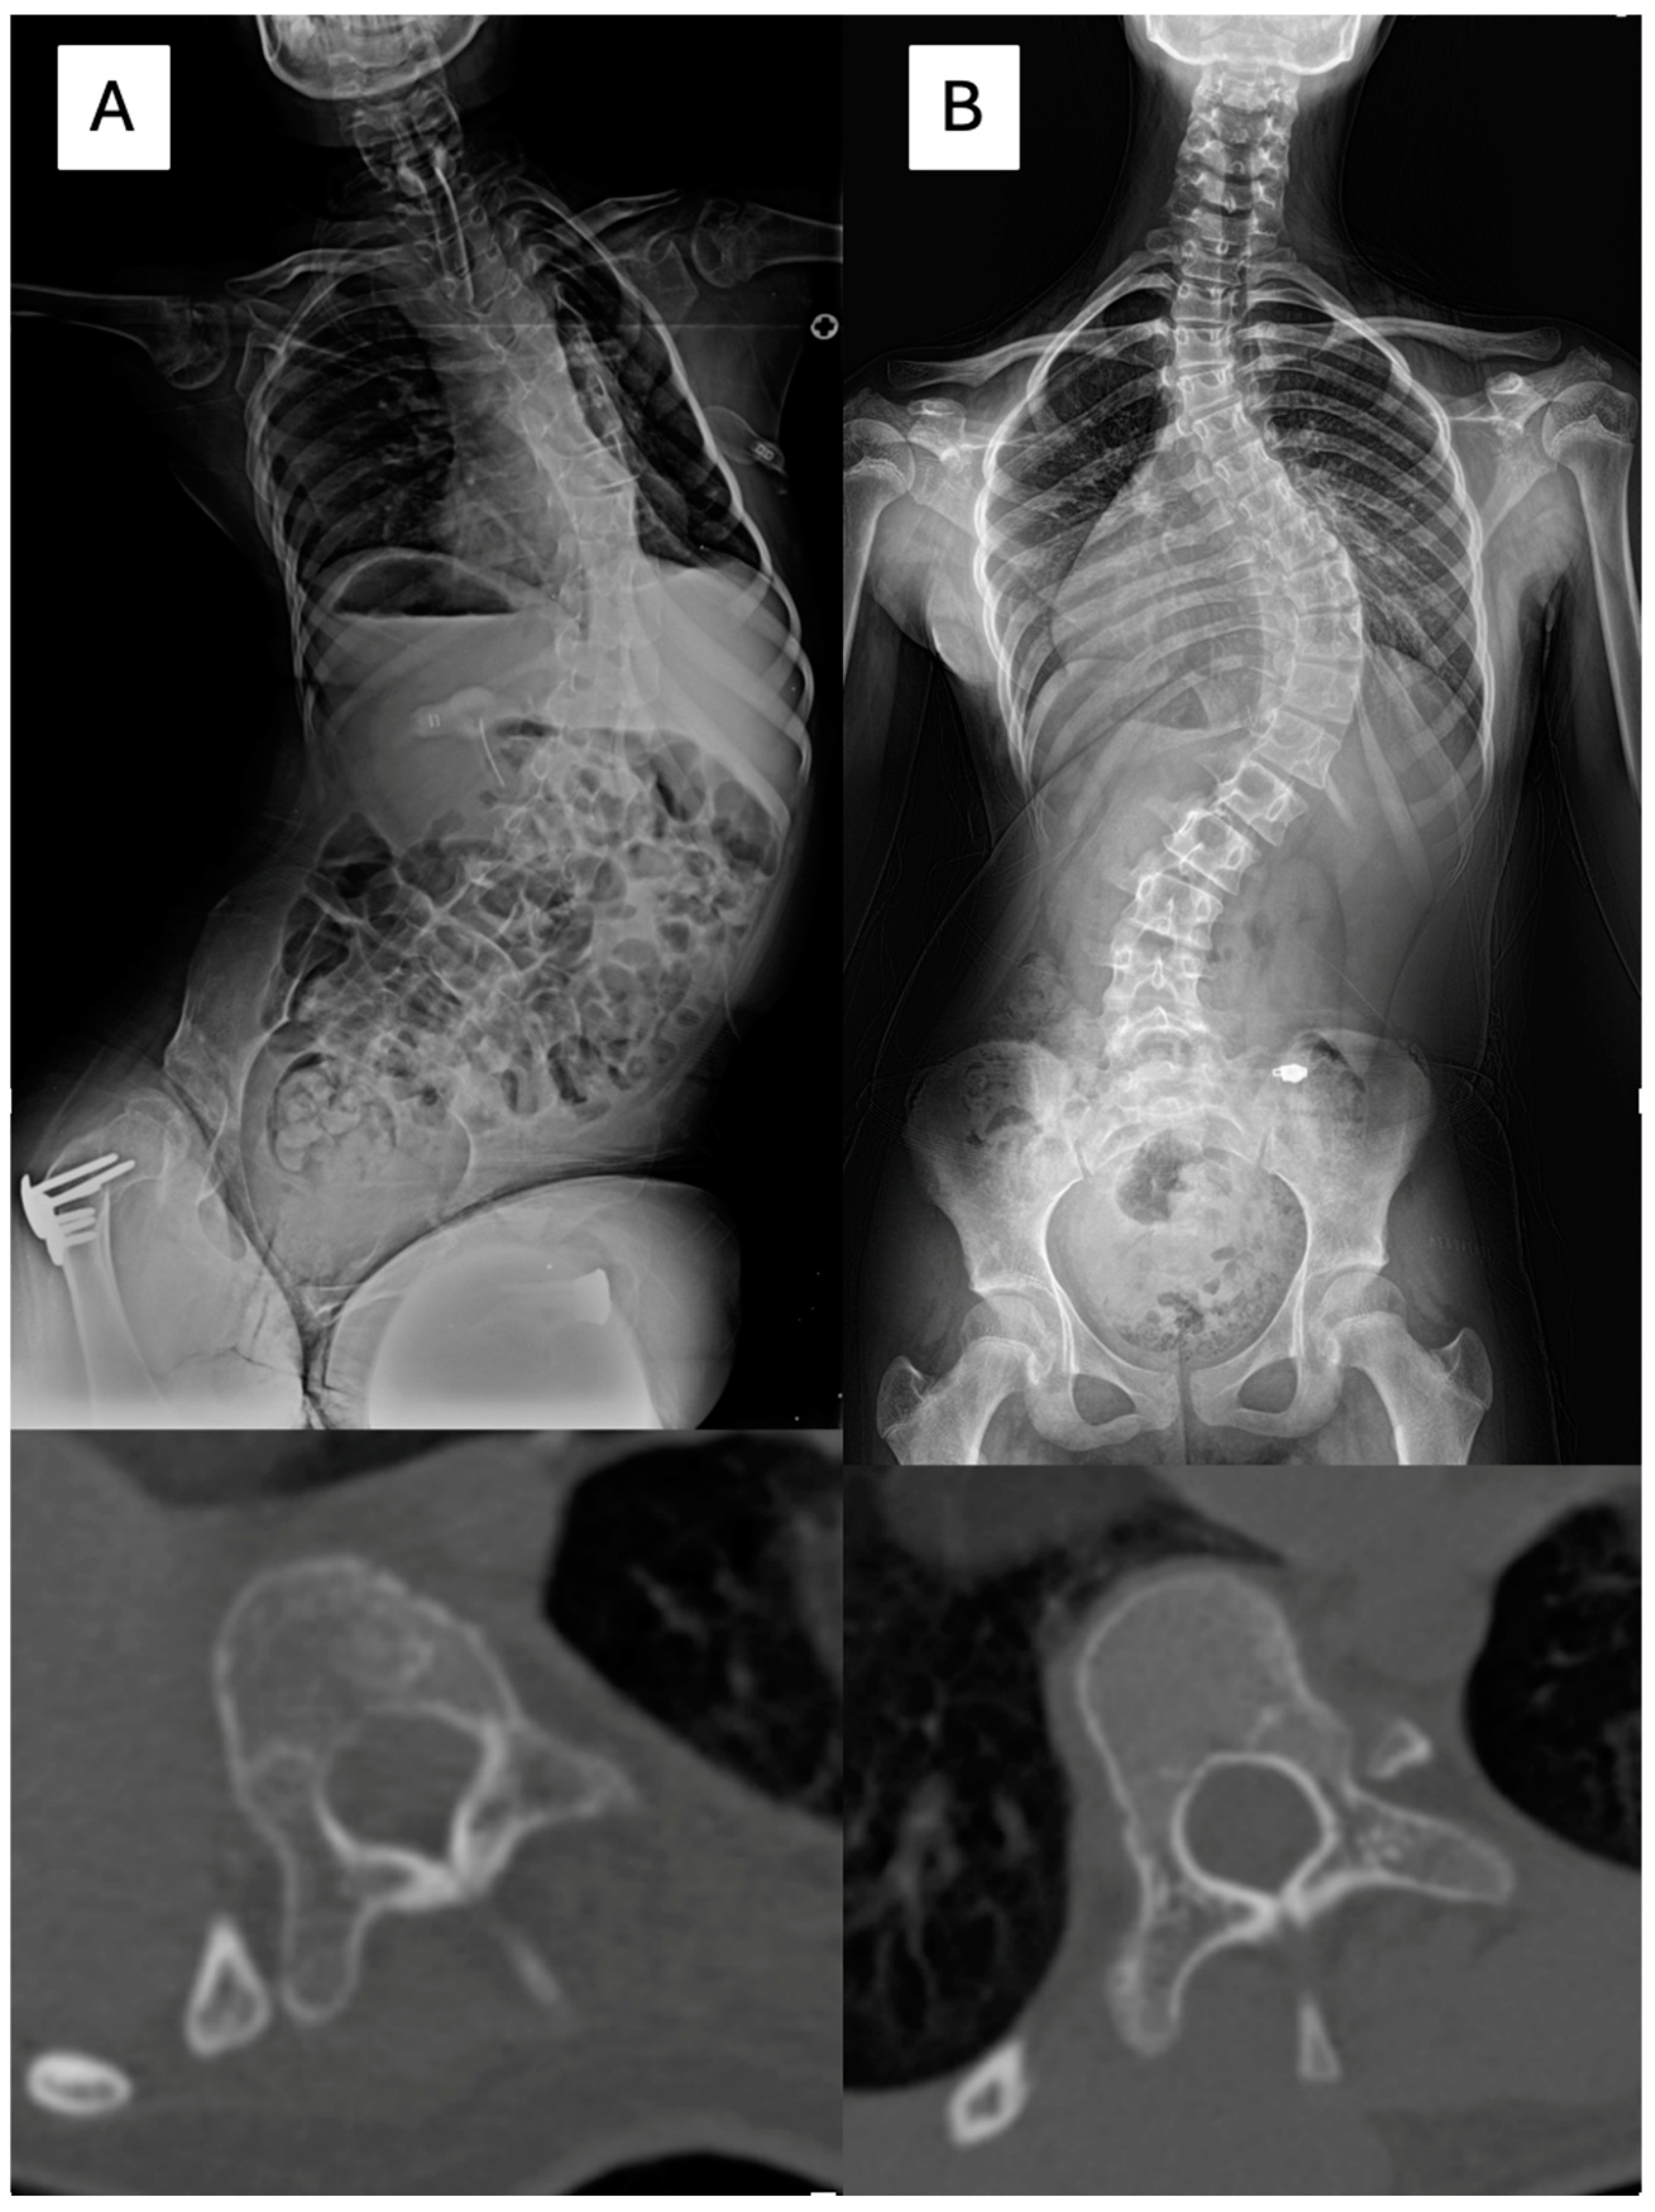

In total, 102 vertebrae with CP scoliosis and 96 vertebrae with AIS were measured. Pedicle diameter (PD), chord length (CL), and vertebral body rotation (VBR) were evaluated one level above the apex, one level below the apex, and at the apex using a reconstructed CT scan [14,17,18,19]. PD was measured in the isthmus region, where the medial and lateral middle cortical borders were the narrowest. The CL was measured as the distance between the posterior cortical entry point of the pedicle and the anterior vertebral cortex in line with the axis of the pedicle. VBR was measured as the angle between the vertical line and the line that bisects the vertebral body (Figure 2). Additionally, the presence of neurocentral synchondroses was investigated (Figure 3) [20,21].

Figure 2. (A) A female aged 10 years and 7 months had neuromuscular scoliosis with spastic quadriplegic cerebral palsy. The Cobb angle between T6 and L4 was 79 degrees, and the apex was T10 (CT). The pedicle diameter and chord length were 3.2 and 24.9 mm at the concave side, and 4.8 and 29 mm at the convex side. (B) An 11 years, 6 months old female was diagnosed with adolescent idiopathic scoliosis with a Cobb angle of 74 degrees (T7-L1) and apex at T10 (CT). The pedicle diameter and chord length were 3.9 and 37.5 mm at the concave side, and 4.8 and 39 mm at the convex side.